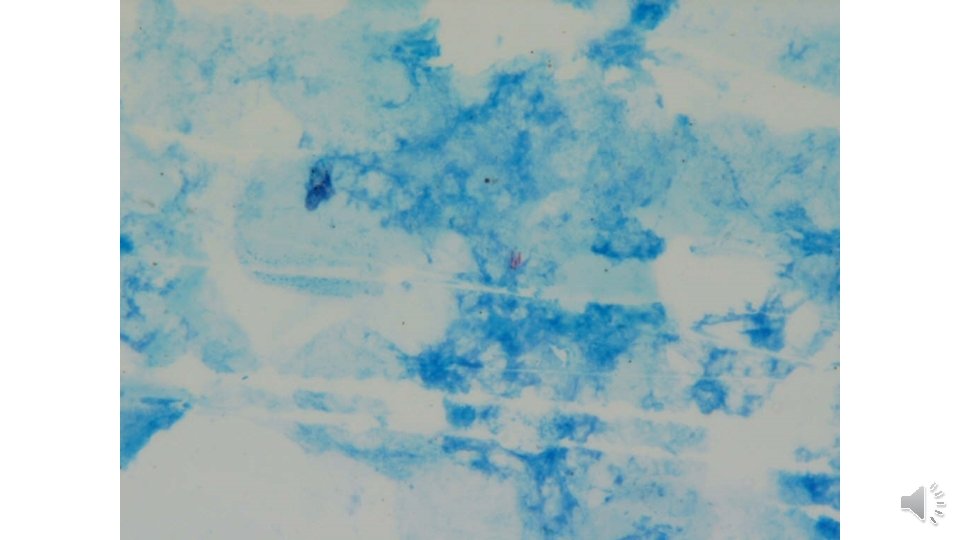

Quantitation scale recommended by the WHO